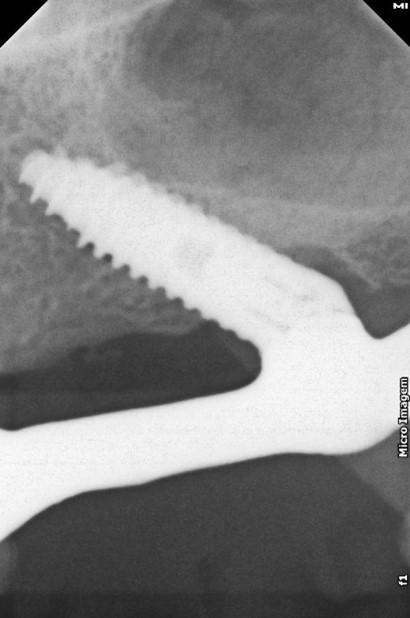

FIG. 12 – Radiografia de acompanhamento de 17 meses após a cirurgia.

A sutura simples dos tecidos foi realizada, seguida pela moldagem de transferência. O plano de cera foi confeccionado, assim como a prova dos dentes em cera, utilizando dentes Vita MFT da Wilcos®. No terceiro dia, a prótese tipo protocolo final foi instalada em carga imediata. O paciente retornou após 10 dias para remoção das suturas. No momento da escrita deste relatório, o caso conta com 26 meses de acompanhamento. Os resultados demonstraram sucesso na osseointegração dos implantes e plena satisfação do paciente, que em três dias já estava reabilitado e utilizando uma prótese fixa sobre implantes, atingindo a expectativa alinhada previamente.